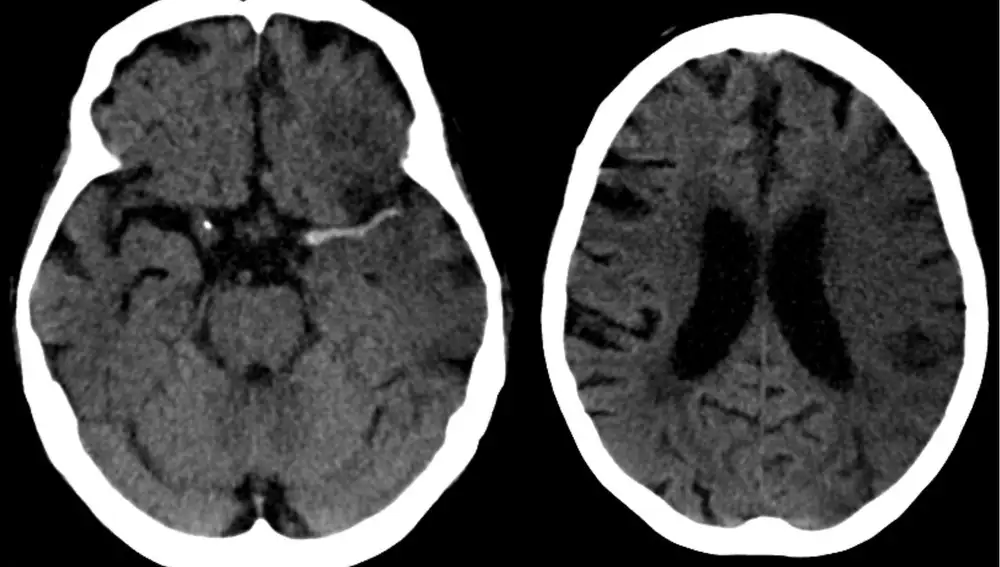

Según la Sociedad Española de Neurología (SEN), una de cuatro personas podría sufrir un ictus a lo largo de su vida. Un ictus ocurre cuando se interrumpe o reduce el suministro de sangre a una parte del cerebro, lo que impide que el tejido cerebral reciba oxígeno y nutrientes causando la muerte de las células cerebrales en pocos minutos.

Normalmente, se trata de un problema que afecta mayoritariamente a las personas mayores. Sin embargo, últimamente los expertos han comenzado a reportar que su incidencia está aumentando entre los más jóvenes. De hecho, según las cifras de la SEN, cada año mueren más de 3.000 jóvenes tras sufrir un ictus.